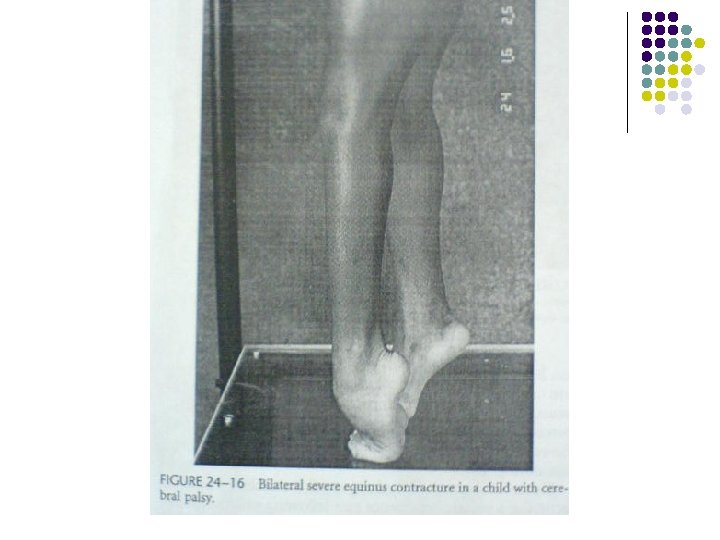

Foot surgery Equinus Ø It is an increased plantar flexion due to a plantar flexion contracture or dynamic plantar flexion due to over activity of the gastrocsoleus during gait. Ø Toe-walking patients must be considered as two different groups: i. equinus patients. ii. as a consequence of crouch at the hip and knee with natural ankle. Ø Cerebral palsy must be differentiated from: A. Idiopathic toe walking as a congenital short Achilles tendon B. Muscular dystrophy (as Duchenn’s)produces toe walking.